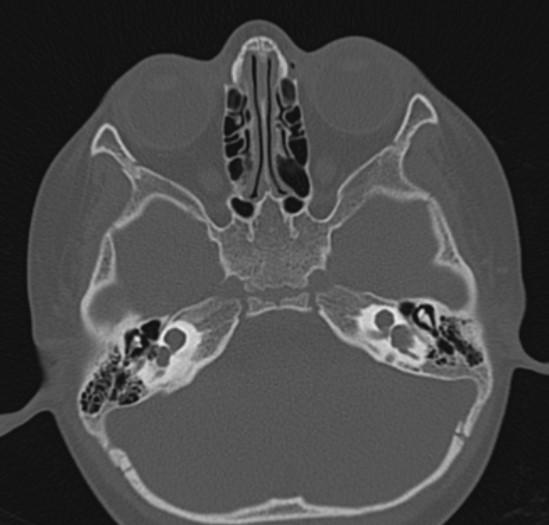

*2-year-old child with hearing loss.

Answer: Bilateral incomplete partition Type I (cystic cochleovestibular anomaly)

Axial MR and CT images show the cystic bilateral cochlea (red arrow) and the dilated cystic bilateral vestibule (yellow arrow). The vestibular aqueduct is normal in size.